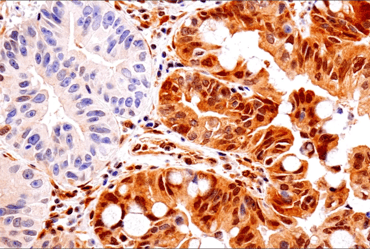

| IHC analysis of paraffin-embedded human non-small cell lung carcinoma using ALK (D5F3®) Rabbit Monoclonal Antibody #3633. | IHC analysis of paraffin-embedded human lung carcinoma using ROS1 (D4D6®) Rabbit Monoclonal Antibody #3287. |

After binding a ligand, RTKs undergo phosphorylation at their cytoplasmic tails (C-termini), which initiates the intracellular signaling. Oncogenic mutations and gene fusions involving RTK kinase domains—for example, CD74‑ROS1, SLC34A2‑ROS1, EML4‑ALK, and NPM‑ALK—can create abnormally active receptors that drive tumor growth. Additionally, in some types of cancer, RTK domains can become uncoupled from the membrane receptor and instead signal in the cytoplasm, allowing them to remain active without growth factor binding or Ras activation.